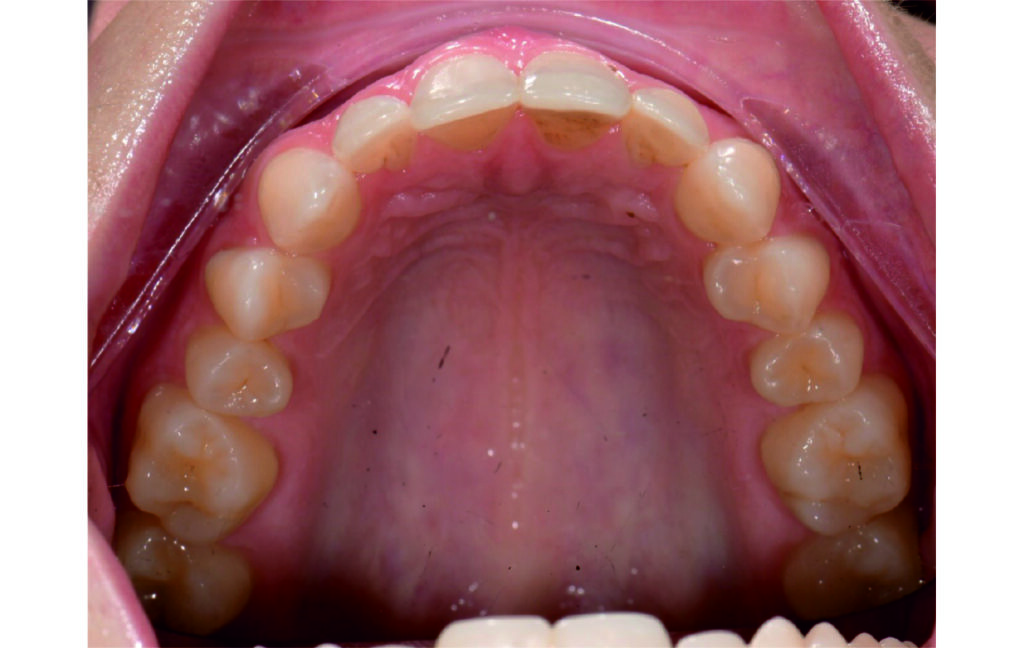

Initial Photos and datas

Angle Class II 2mm on the right, Angle Class II 2mm on the left, light mandibular asymmetry to the right, lower central line 1mm to the right, upper central line 1,5mm to the left, 1mm overjet and overbite. Sagittal asymmetry of upper dental arch. Light crowding upper and lower frontal segments, severe attrition of posterior teeth, night bruxism. Normal sagittal position of both jaws, high angle case, steep mandibular ramus,excessive lower facial height, open bite tendency.

The case initially presented as a moderate Class II on the right and a Class II tendency on the left, with tapered dental arches and an anterior open bite extending to tooth 26 in segment II.

In segment I, the open bite reached up to the first premolar.

A 1.5 mm deviation of the upper dental midline to the patient’s left was noted, along with a slight mandibular midline shift to the right, likely due to asymmetrical mandibular growth observed in the facial structure. Severe mesial rotations of teeth 16 and 26 were evident in the initial records. As derotation of 16, 26, 17, and 27 progressed up to aligner 16, the premolars in segments I and II moved distally, resulting in a bilateral Class I relationship, as intended in the initial treatment plan.